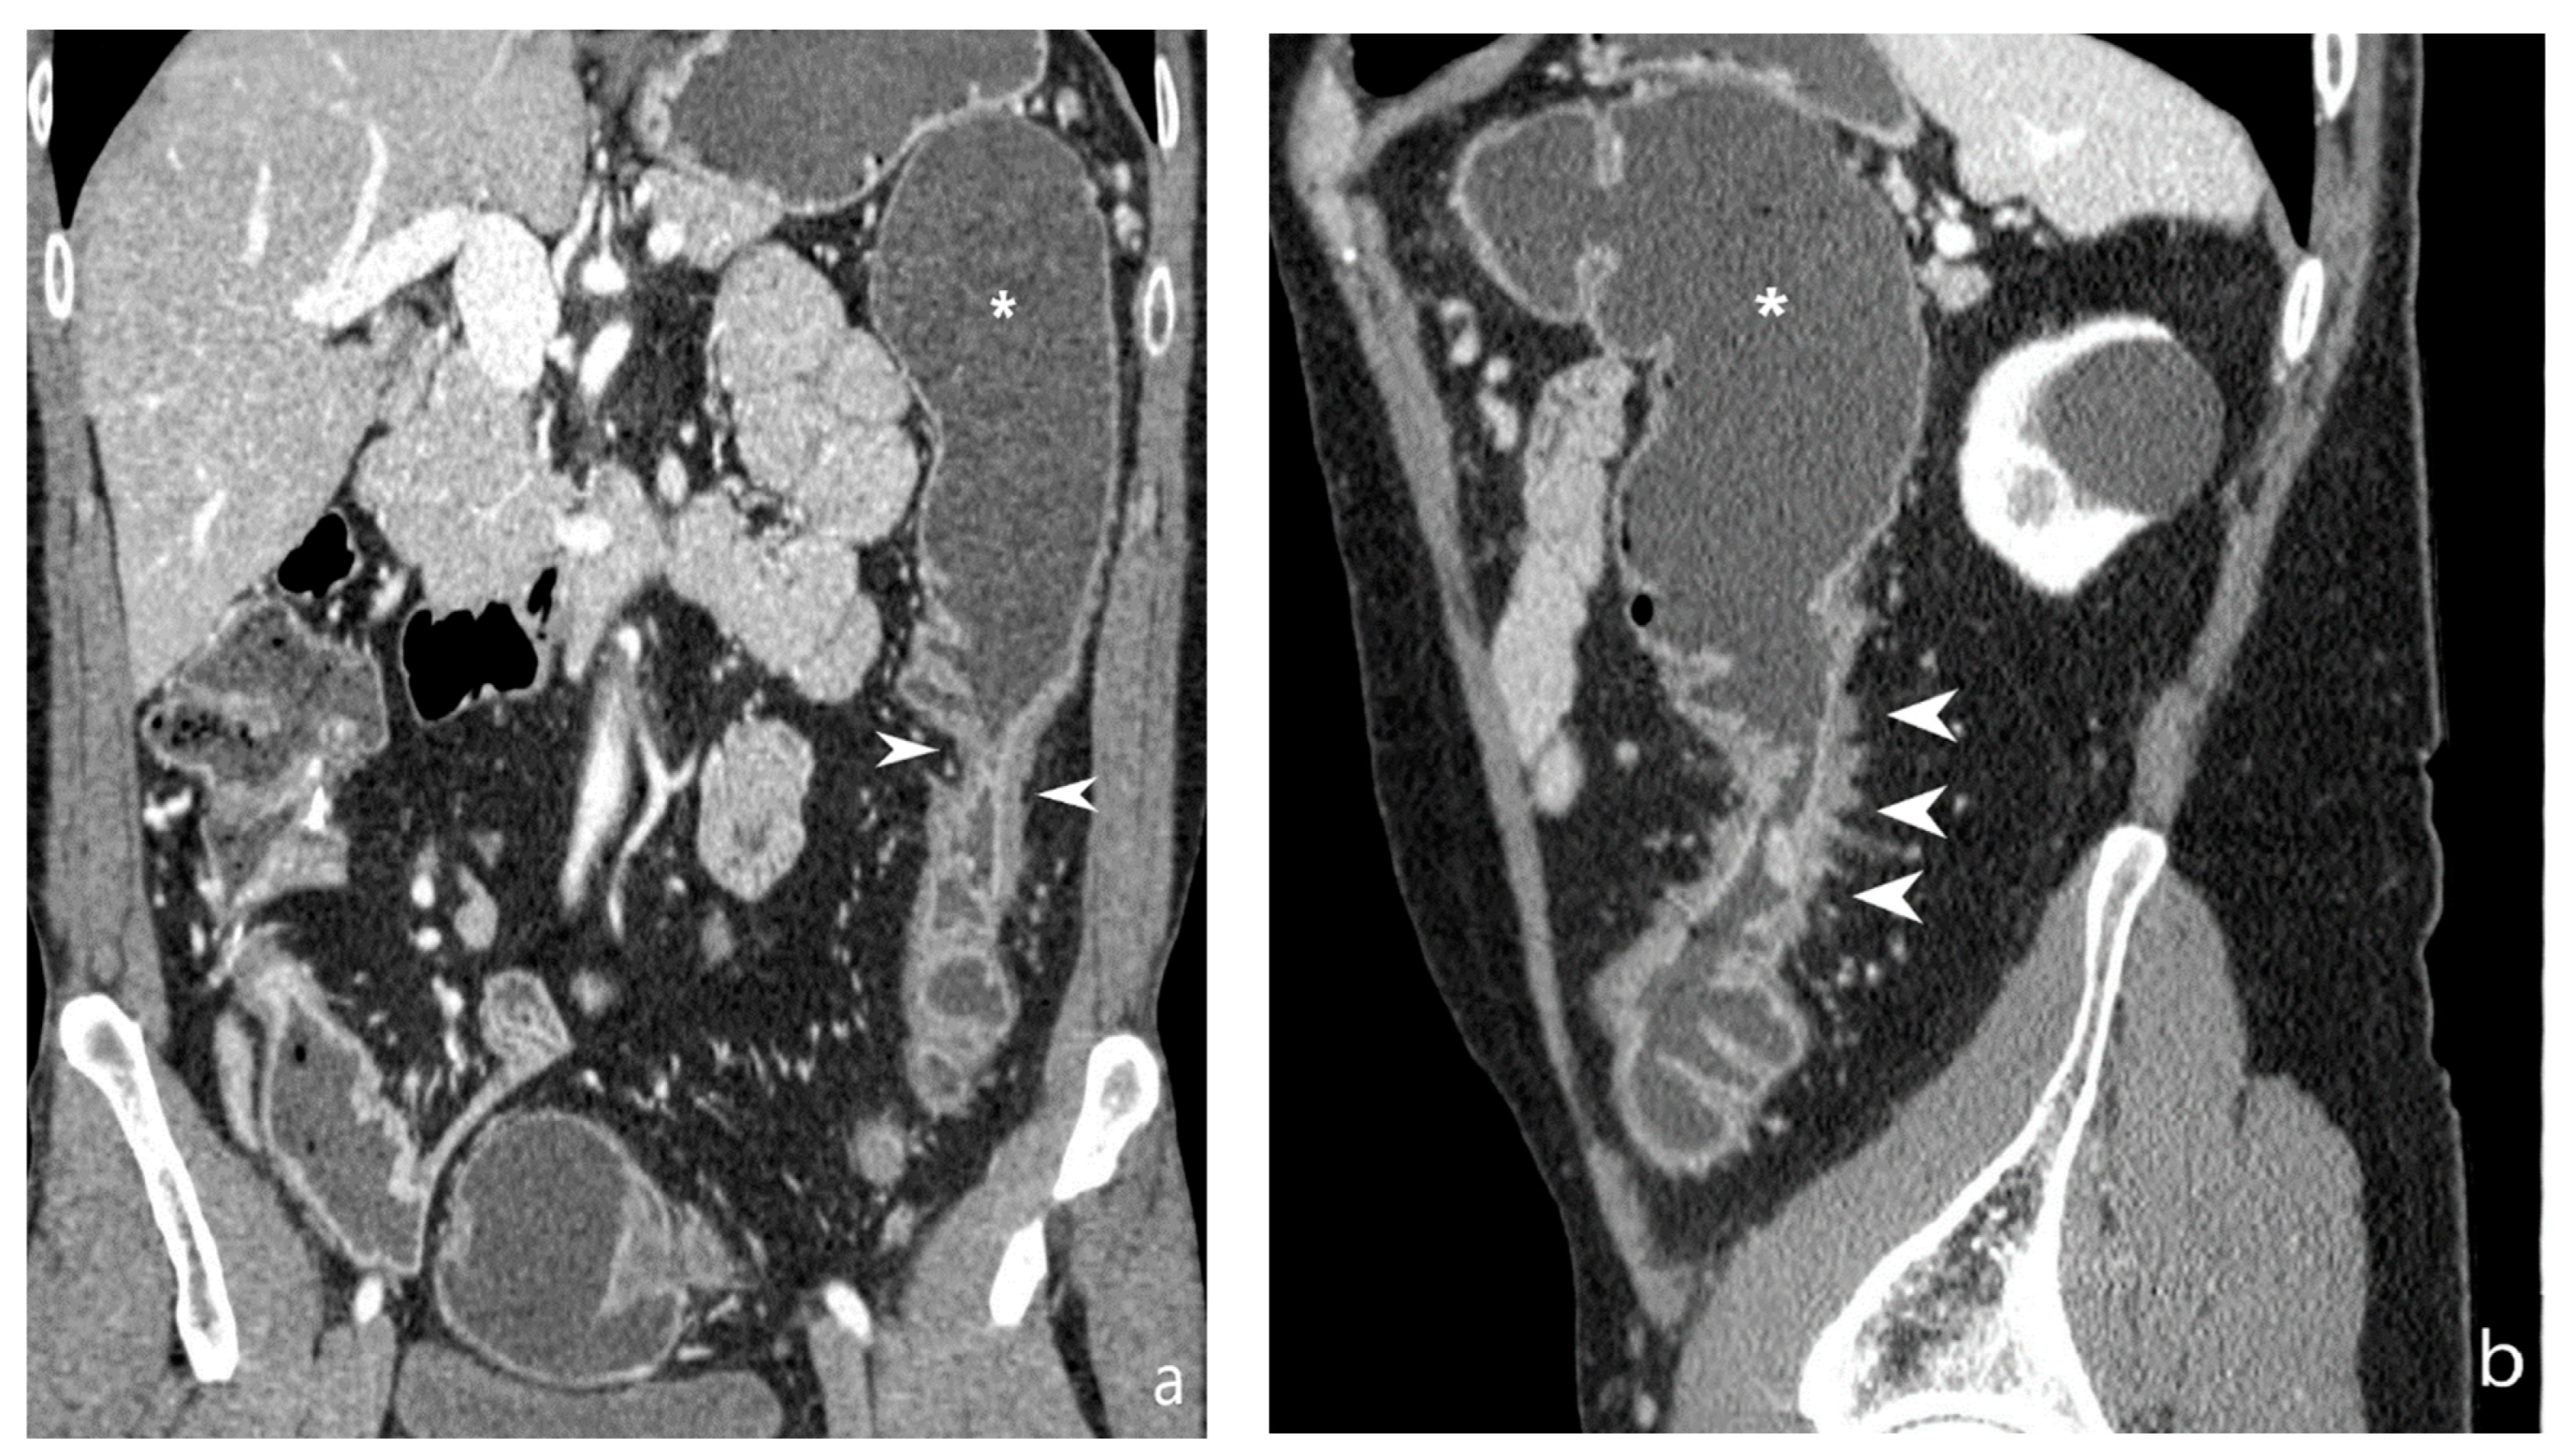

5.2. Fibro-Stenotic Subtype

6. Is It Possible to Identify the Presence of Strictures and to Discriminate Inflammatory from Fibrotic Ones?

6.2. Differentiation between Fibrotic or Inflammatory Stenosis